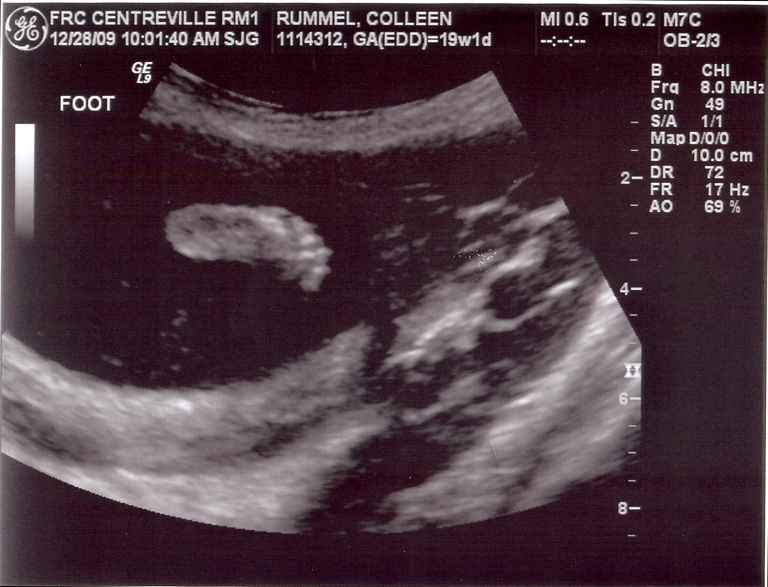

*pay no attention to the negligent mother hiding behind the computer screen*

I really and truly have been meaning to post these. But I really and truly did have an issue with my scanner. I would attempt to scan the images and it would say “uh, I’m sorry, which computer would you like these sent to?” and I’d remind it nicely that it would be for my cute little laptop. Then the scanner was all “whatever,” and wouldn’t send the images to my laptop. So I tried to dupe it by triggering the scanner remotely from my laptop (instead of the scanner itself), and I’ll be darned if the thing didn’t holler out at me “B**** please! I can see you in there!” and wouldn’t send me the images. So I was forced to ask Justin a few times to scan the sonogram images for me. I think I literally heard the scanner purr “oh, the Apple wants some images scanned? Sure! Whatever you want, sweetie!”